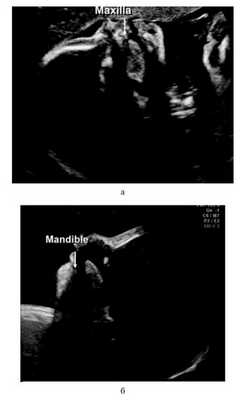

Эхографически обследованы 2078 беременных женщин, находящихся на 20—22-й неделе гестации. Выявлено 8 плодов с РГН (1:300 новорожденных!). Во время проведения эхографического исследования язык плода был объектом особого интереса. У здорового плода верхушка языка ориентирована к небу; у плода с выявленной расщелиной губы она визуализируется у основания альвеолярного отростка нижней челюсти. Отмечается эхогенная зона между поверхностью языка и небом (рис. 7). Рисунок 7. Результаты эхографического исследования плодов на 20-й неделе гестации. а — положение языка у здорового плода, б — положение языка у плода с РГН.

В 2 случаях у плодов с аномальным положением языка не было эхографических признаков расщелины губы, после родов у этих детей была диагностирована изолированная расщелина неба (рис. 8). Рисунок 8. Клиническое наблюдение. а — плод без эхографических признаков расщелины губы; б — новорожденный; в — расщелина неба.